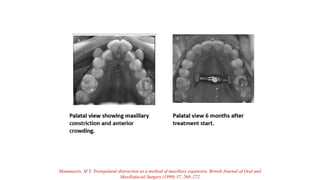

Mommaerts. M Y. Transpalatal distraction as a method of maxillary expansion. British Journal of Oral and

Maxillofacial Surgery (1999) 37, 268–272